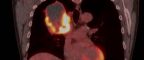

The LCCE, led by Professors Caroline Dive and Charles Swanton, was established in 2014 as a key component of CRUK’s renewed focus on tackling the unique complexities of lung cancer. Over the past decade, it has become a hub of incredible research developments, playing a role in findings like those of the TRACERx study, which showed that air pollution can cause inflammation leading to non-small cell lung cancer, a discovery which will have significant implications for public health and prevention strategies.

And, since funding for the LCCE was last renewed in 2019, its researchers have developed more than 15 computational tools to help understand how tumours evolve over time. These include blood tests to analyse the immune system and reveal the genetic changes driving lung cancer. Advances like these could help save lives by allowing doctors to diagnose the disease earlier, when treatments are most likely to be effective.